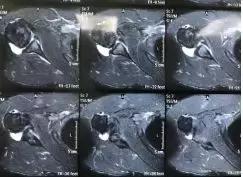

右肩关节磁共振影像